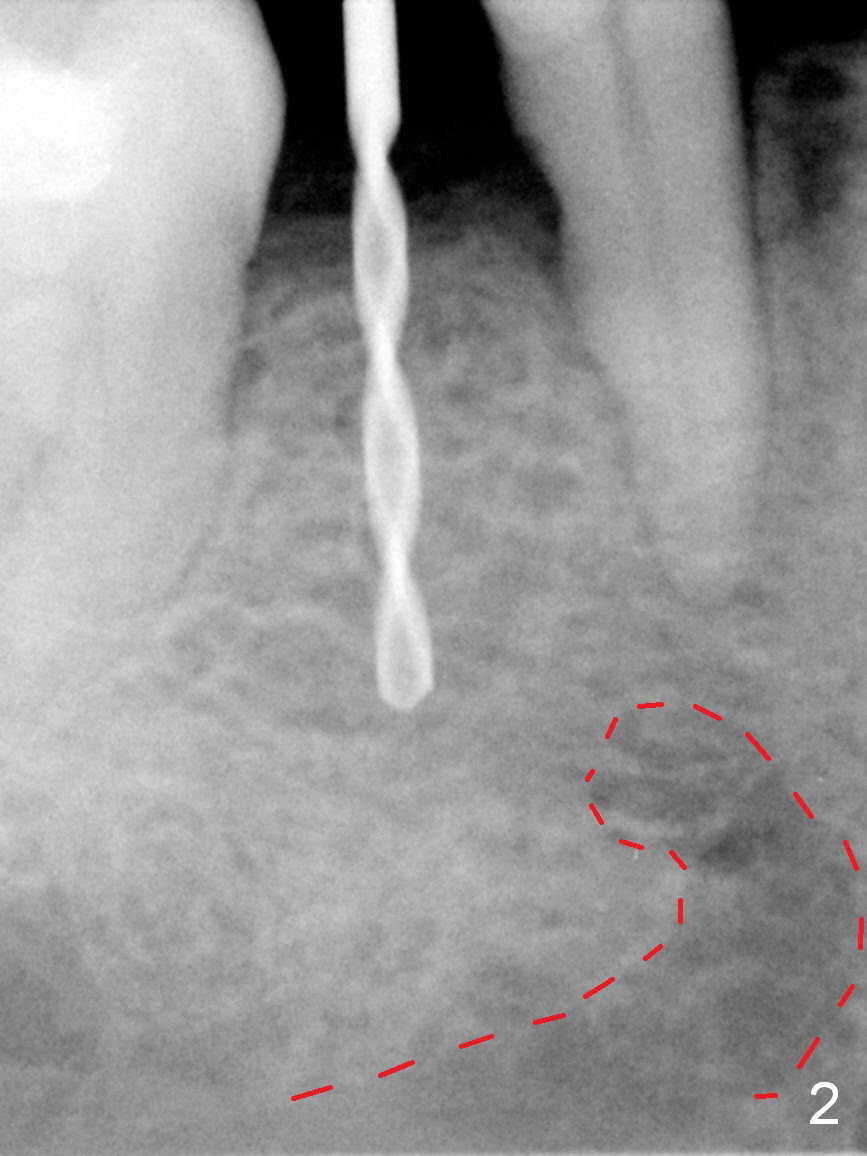

Mesialization of the tooth #29 consists of open coil spring distal (Fig.1 ^) and closed coil spring mesial (^^^). Due to limited time and incompliance, the mesialization is incomplete (Fig.3 *). Total treatment lasts 1 year. The mesial surface of the #29 (Fig.3 <) and the distal surface of #31 are trimmed before incision. The mesiodistal width increases from 5 mm to 6 mm. In fact the ridge is not too narrow buccolingually when an incision is made (Fig.3). There is bone buccal and lingual to a 2.5 mm osteotomy (Fig.3) after adjustment of its initial one with 1.2 mm pilot drill (Fig.2 (red dashed line: the Mental Loop). A 3x12(2) mm 1-piece implant is placed (Fig.4) with insertion torque > 40 Ncm. GBR is also done to increase ridge width.